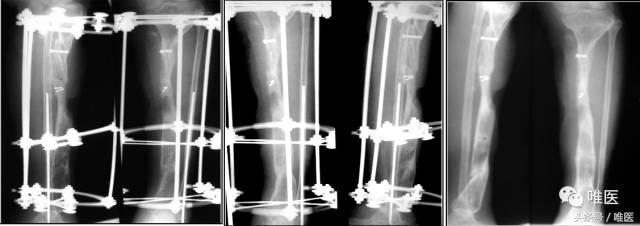

二期:一期术后6个月,两骨断端逐渐靠近、重叠到位后,再行左胫骨中上段断端修整、重叠对合,髂骨植骨螺钉固定,继续外架保护固定。

7. 术后随访

二期术后12月:骨缺损完全修复,外架拆除后。

二期术后12月:功能恢复良好